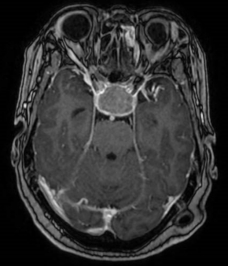

听神经瘤术前核磁 术后CT